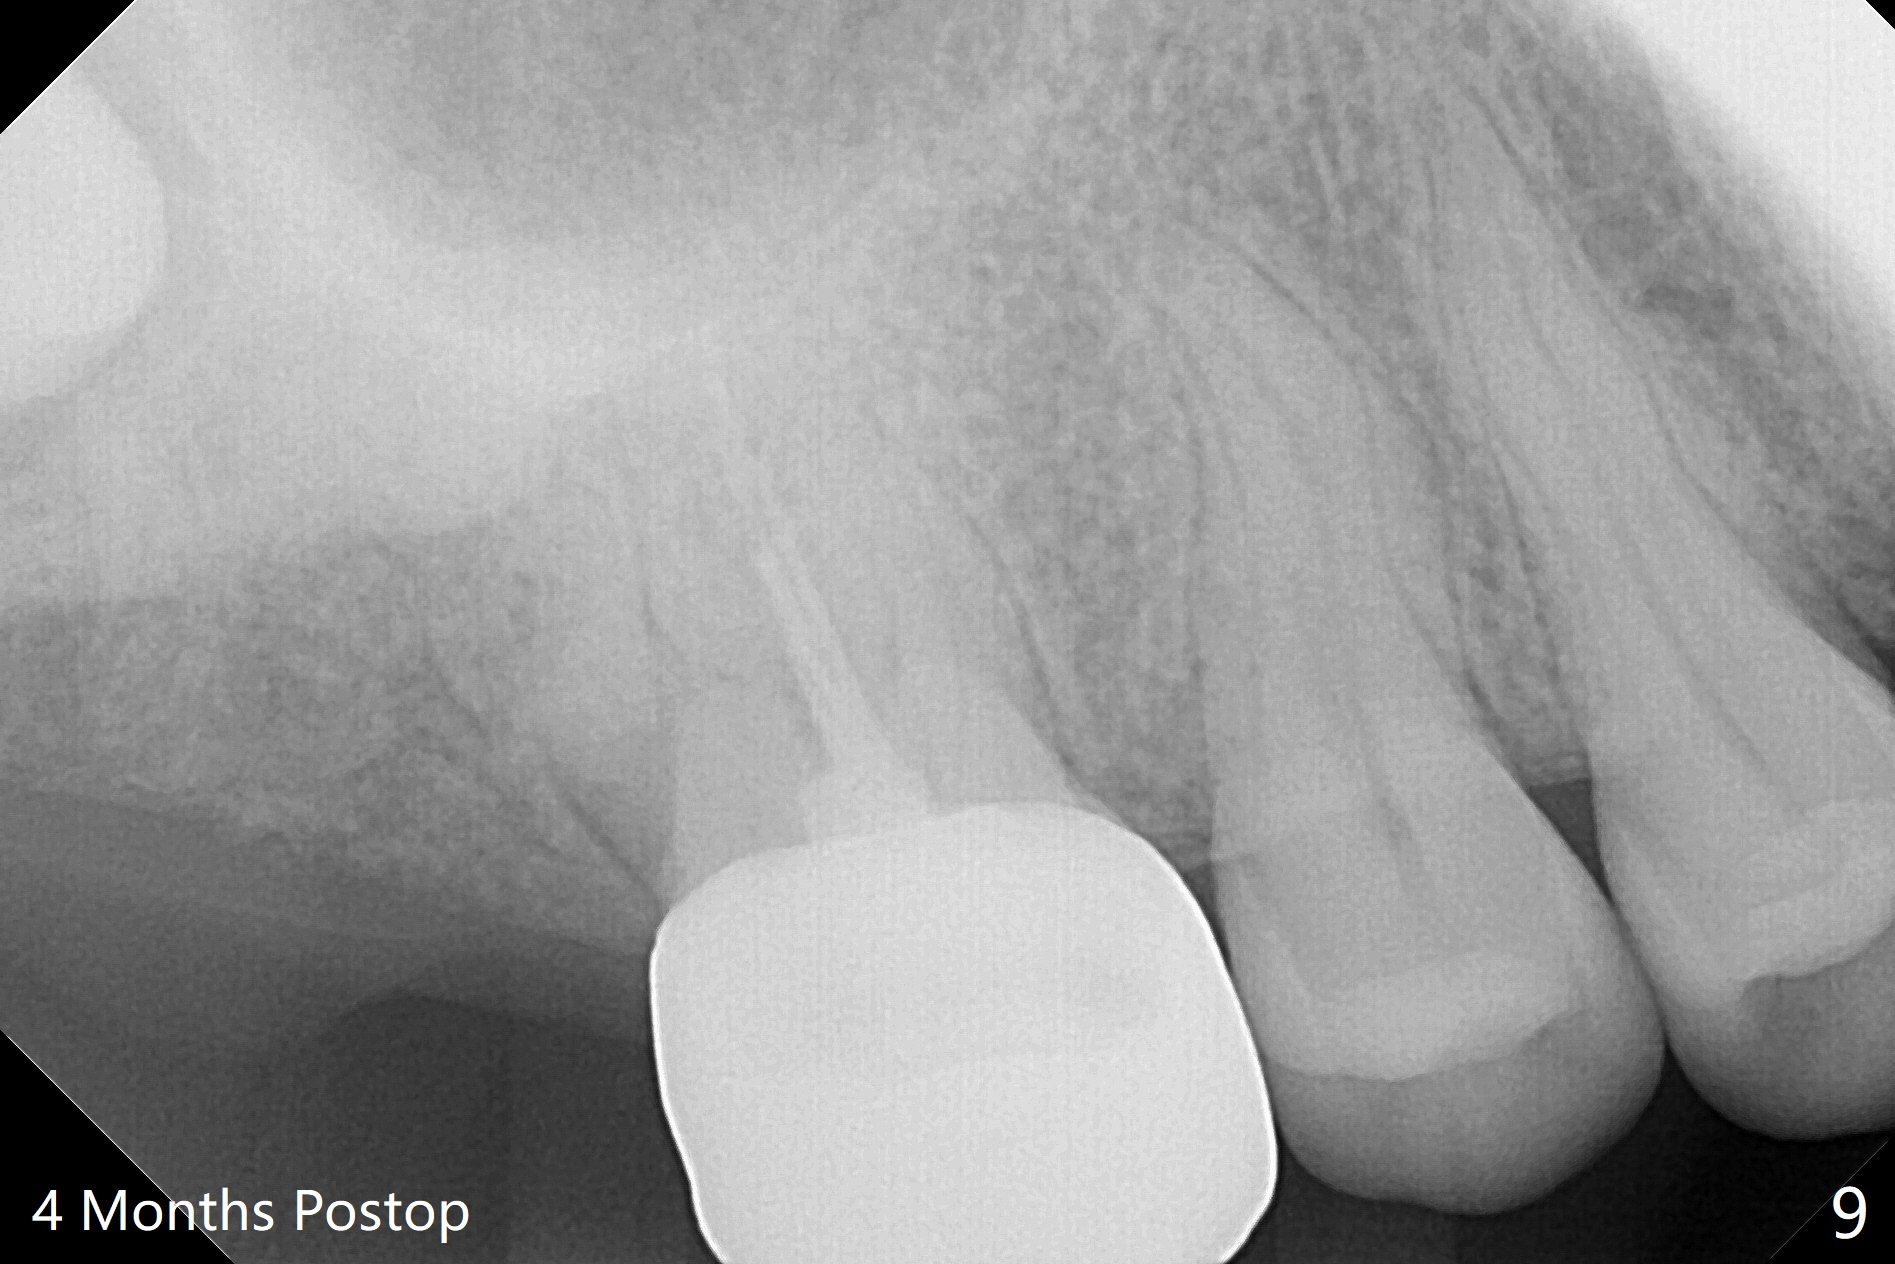

The socket of #2 heals 13 days postop; it appears that the bone graft remains in place (Fig.7,8 *). The patient is instructed to return in 3-4 months for impression and CT for guide. The socket heals 4 months postop (Fig.9,10). She plans to have implant next year, since she wants to add another insurance. The patient returns for implant without removal of the third molar 2 years 4 months post socket preservation (Fig.11). A 5x7.3 mm implant can be placed without invading the sac of the impacted third molar (Fig.12). In fact the lab has a better plan. A lump of bone forms in the previous socket 1 year 4 months postop (Fig.13 *). The ridge is wide and dense (Fig.14). A narrow implant placed oblique could be longer (Fig.15), as compared to a wide, short one (Fig.12).